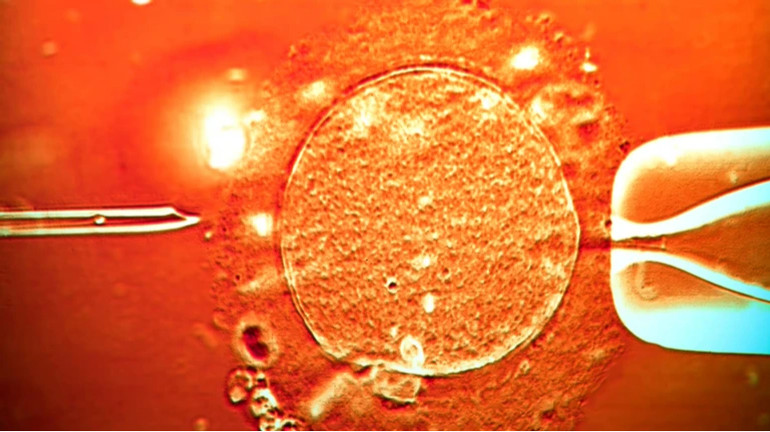

Біологічний матеріал від донора з 2005 року отримував Європейський банк сперми. Згодом зразки використовували для процедури жінкам протягом близько 17 років.

Донор був здоровим і пройшов перевірку, однак виявилося, що він мав мутацію ДНК. Через це у чоловіка був пошкодженим ген TP53, який відіграє вирішальну роль у запобіганні виникнення ракових клітин. На момент донорства мутація не вважалася онкогенною.

Тепер відомо, що діти, народжені з ураженої сперми (небезпечну форму TP53 містять до 20% сперматозоїдів), мають мутацію в кожній клітині тіла. Цей стан відомий як синдром Лі Фраумен – важке спадкове ракове захворювання. Хворі мають ймовірність до 90% розвитку онкології в дитинстві та раку молочної залози.